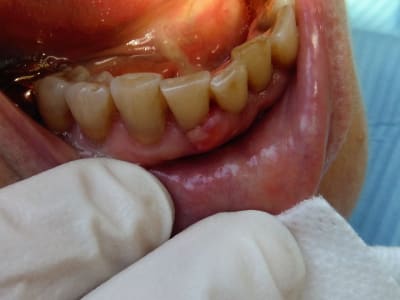

Imagine!

Dscf3075 xeeon3 - Eugenol

Allez, pas la même teinte, pas la même forme, forme irrégulière d'ailleurs, mal délimité, apparition récente et évolutive.

Patiente fumeuse...

C’est un carcinome

le prélèvement a parlé, carcinome épidermoîde, bad news...

la photo est pas top... 2017 apn de plage, mais la plupart du temps ça ressemble à rien un carcinome.